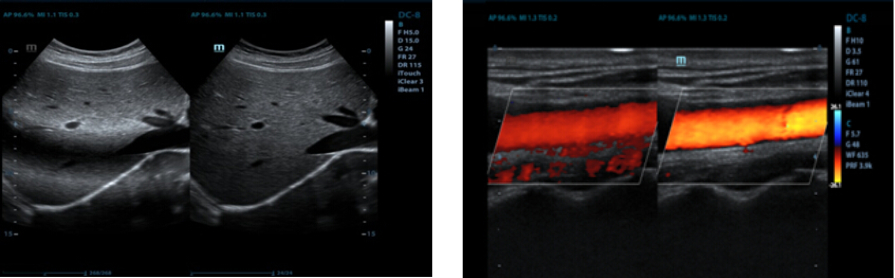

Auto IMT (espesor de la media e íntima)

La medición automática del espesor de las paredes anterior y posterior proporciona un estado preciso de la carótida.

3D en color

Analice los vasos ramificados con eficacia gracias al Doppler 3D en color (disponible en 3D est√°tico, solo con D6-2E).

Mejora del microflujo

Vea mejor las perfusiones de los vasos peque?os y mejore su comprensión de la vascularidad de la patología mediante el uso de varios marcos para generar imágenes acumuladas.